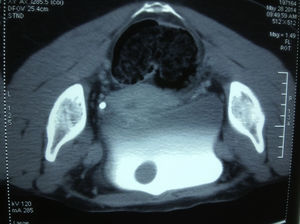

Descripción de caso clínicoPaciente femenino de 34 años de edad, quien se presenta en nuestro centro en busca de segunda opinión médica, ya que durante un ultrasonido de control de embarazo (fig. 1) se reporta la presencia de pólipo vesical, por lo que, una vez concluido el embarazo (cesárea, 22 de marzo del 2014), se le solicitó una tomografía de abdomen y pelvis simple y con contraste intravenoso (figs. 2 y 3), la cual muestra imagen de lesión tumoral polipoide de base amplia, de 2cm de diámetro y contorno bien definido, dependiente del techo a la izquierda de la línea media.

Al momento de nuestra primera revisión, 2 semanas posterior a la RTU, la paciente se encuentra asintomática; de igual forma, niega sintomatología preexistente durante su revisión de rutina ginecoobstétrica en el momento de diagnóstico de lesión vesical. Además, cuenta con el antecedente de reemplazo hormonal por tratamiento de infertilidad, consiguiendo finalmente este último embarazo. Se procede a revisar las imágenes de tomografía, reporte de patología, sin dejar de lado el cuadro clínico de la paciente (asintomática, sin hematuria ni dolor); sin embargo, no se logra hacer correlación, ya que la imagen por tomografía no corresponde a un carcinoma de urotelio in situ, siendo la observada de tipo polipoide, y bien delimitada, y al menos no correspondiente con un estadio in situ, como se observa en las figs. 1–3, por lo que se solicita revisión de laminillas con el departamento de Patología, que reporta: proliferación fascicular compacta nodular de músculo liso sin atipia, ni actividad mitósica, indicativa de tumor benigno de músculo liso. La biopsia de cúpula vesical presenta hiperplasia urotelial plana. El urotelio, compuesto por entre 7 y 9 capas de células, sin atipia, y que conserva las células superficiales «en sombrilla». Esto se hace evidente por medio de la inmunomarcación con CKZO, que únicamente marca las células superficiales. Llama la atención que por debajo del urotelio hiperplásico hay proliferación fascicular, nodular y células de músculo liso que expresan tanto actina como desmina, con un Ki67 bajo, lo cual indica leiomioma (fig. 4 a-d).

El diagnóstico suele ser incidental mediante tomografía computarizada, evidenciando una imagen homogénea sólida con márgenes bien definidos, tal como se observa en este caso clínico; la resonancia magnética resulta ser de mayor utilidad, permitiendo demostrar su origen en la submucosa y la preservación de la capa muscular6. Sin embrago, el diagnóstico definitivo continúa siendo mediante el estudio histopatológico7-11 e inmunohistoquímica positiva para tejido muscular (desmina, actina, act HHF-35).